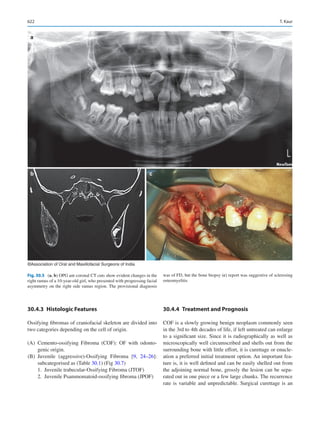

lent in many countries. Several patients are aware of which

chemotherapy may be best effective for the management of

1  Oral and Maxillofacial Surgery in India: How Did We Get Here and Where Are We Going?

6